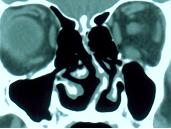

鼻中隔偏曲--類型按偏曲的形狀,鼻中隔偏曲可分為:

1.“C”形偏曲:鼻中隔凸向一側,常僅限於軟骨部,也可為軟骨和篩骨正中板同時向一側偏曲。

2.“S”形偏曲;篩骨正中板偏向一側,而中隔軟骨偏向對側。

3.嵴突:鼻中隔上的長條形隆起,自前下向後上走行。多位於上頜骨鼻嵴或犁骨上緣。有的嵴突為軟骨脫位重疊所造成。

4.棘突(距狀突):為局限性尖銳突起,常位於中隔軟骨與骨部接合處。

按偏曲的方向分類,有縱偏、橫偏和斜偏。按偏曲的部位分類,可分為高位、低位、前段、後段偏曲。